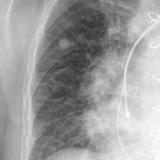

APE 3

Date: 11/05/2005

Views: 4001